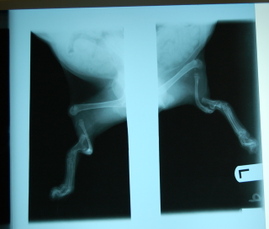

Tibby_and_fibby_xrays_2

So here’s a close-up of the X-ray that was on the lightboard, showing both limbs.  With the tibia completely malformed and the fibula entirely missing, we figured Tibby and Fibby seemed like appropriate names for these two … as Chris said, to give them back at least in name and spirit.